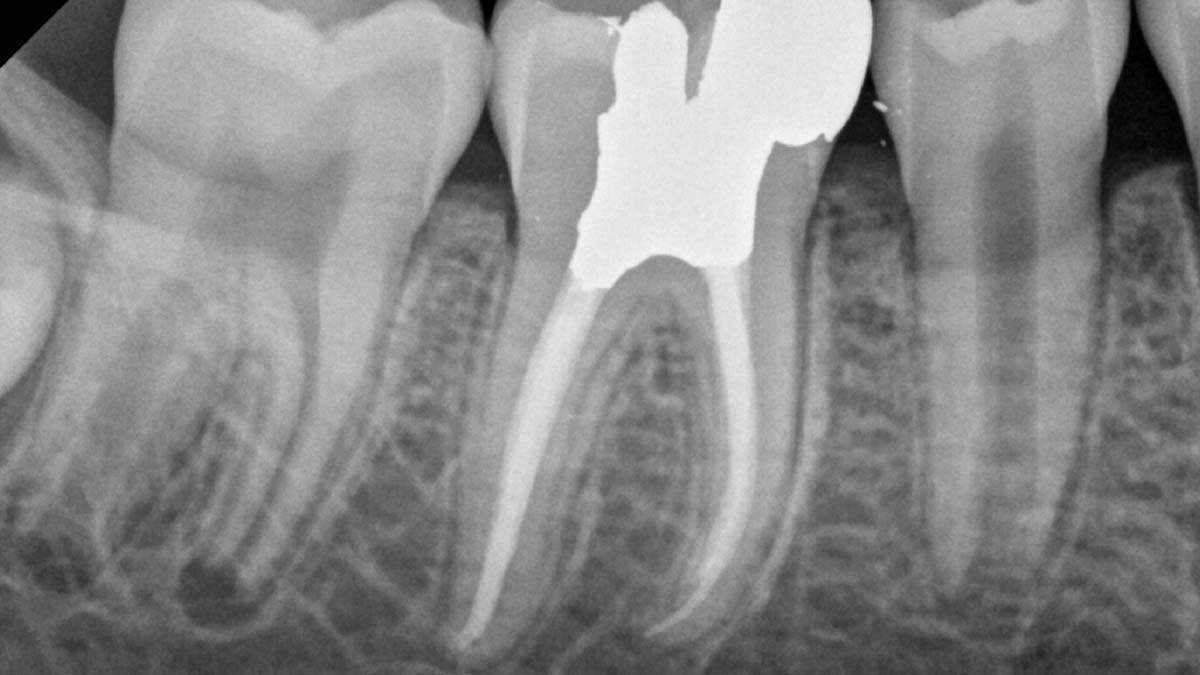

On the right: Gutta-Smart and Conform Fit feature the same advanced gutta-percha for radiographic consistency.

Image courtesy of Dr. Nathaniel Behrents, Fayetteville, AR